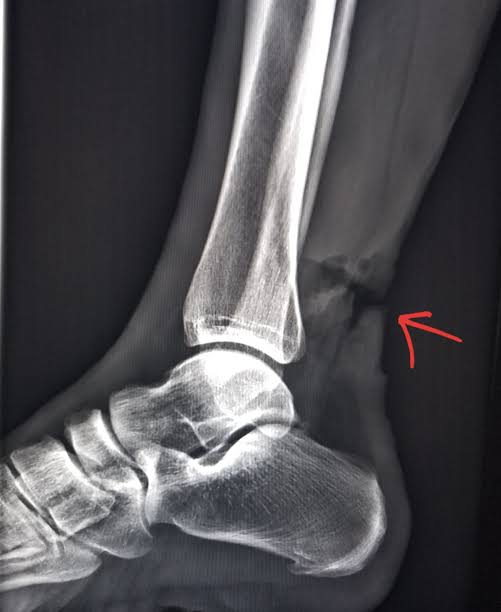

Achilles Tendon Injury X Ray . There is a complete tear of achilles tendon approximately 6 cm away from the insertion site. The radiographs demonstrated obliteration of kager's fat pad, a finding highly suspicious for an achilles tendon rupture (figures 1 and 2). Achilles tendon ruptures are common tendon injuries that occur due to sudden dorsiflexion of a plantarflexed foot, most commonly associated with sporting events. Evaluation of heel pain can be clinically challenging, and. The achilles tendon originates in. The gap between the two edges. There was tenderness at the lateral malleolus, and ankle range of motion (rom) couldn't be elicited due to injury. 1 kager's fat pad, located. Therefore, we review the anatomy, mr imaging findings, and pathologic findings in an attempt to develop a systematic nomenclature. Achilles tendon tears are the most common ankle tendon injuries, with microtears to full thickness tendon tears of the achilles tendon and are most commonly seen secondary to.

Investigating the Validity of Soft Tissue Signs on Lateral Ankle XRay Achilles Tendon Injury X Ray Evaluation of heel pain can be clinically challenging, and. The radiographs demonstrated obliteration of kager's fat pad, a finding highly suspicious for an achilles tendon rupture (figures 1 and 2). There is a complete tear of achilles tendon approximately 6 cm away from the insertion site. Therefore, we review the anatomy, mr imaging findings, and pathologic findings in an attempt. Achilles Tendon Injury X Ray.